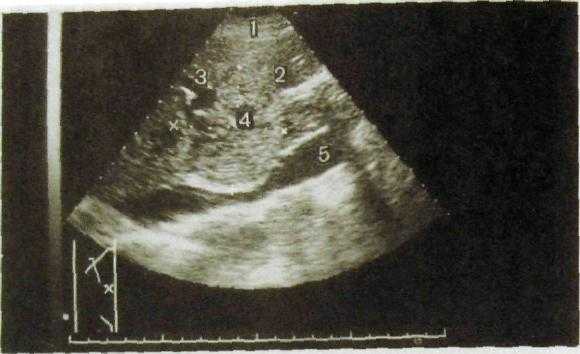

Большинство доброкачественных опухолей печени — гемангиомы, реже встречаются аденома и узловая гиперплазия. На сонограммах они видны как гиперэхогенные образования округлой или овальной формы с четкими контурами и однородной структурой (рис. Ш.139). На компьютерных томограммах гемангиома обусловливает ограниченный участок пониженной плотности неоднородной структуры с неровными очертаниями (рис. III. 140). При усиленной КТ отмечается увеличе-

Рис. HI. 139. Сонограммы печени (две проекции и схемы к ним). Гемангиома.

1 — гемангиома; 2 — тромб в ветви воротной вены; 3 — стенки правой ветви воротной вены; 4 — диафрагма.

Гепатоцеллюлярный рак (гепатома) обусловливает на сонограммах участок неравномерной плотности с неровными контурами (рис. Ш.141). Распад опухоли выглядит как эхонегативная зона неправильной формы, а отек вокруг опухоли — как расплывчатый ободок, тоже эхонегативный. На компьютерных, магнитно-резонансных томограммах и сцинтиграммах (эмиссионных томограммах) гепатома обусловливает дефект неправильной формы с неровными очертаниями (рис. III. 142).